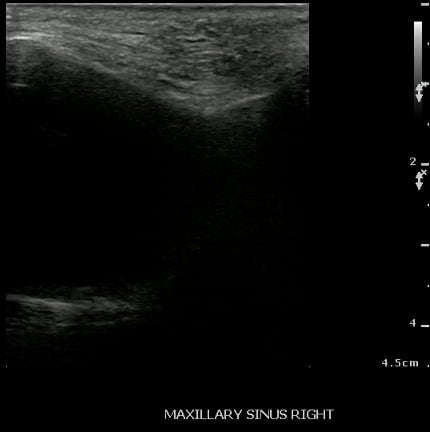

- Normal Maxillary Sinus:

- The normally air-filled maxillary sinus prevents the transmission of ultrasound beams (Air reflects most of the signal, thus preventing visualization of deep structures).

- The anterior maxillary sinus wall produces a bright echo in the near field, with reverberation artifact posteriorly (producing a snowstorm appearance), and preventing visualization of the posterior wall.

- Figure 27 and 28. Normal maxillary sinus